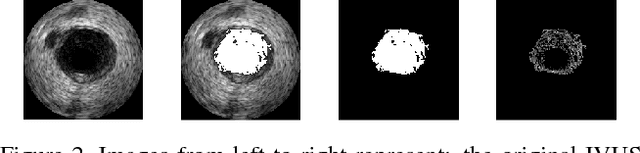

Abstract:This work concentrates on Extremal Regions of Extremum Level (EREL) selection. EREL is a recently proposed feature detector aiming at detecting regions from a set of extremal regions. This is a branching problem derived from segmentation of arterial wall boundaries from Intravascular Ultrasound (IVUS) images. For each IVUS frame, a set of EREL regions is generated to describe the luminal area of human coronary. Each EREL is then fitted by an ellipse to represent the luminal border. The goal is to assign the most appropriate EREL as the lumen. In this work, EREL selection carries out in two rounds. In the first round, the pattern in a set of EREL regions is analyzed and used to generate an approximate luminal region. Then, the two-dimensional (2D) correlation coefficients are computed between this approximate region and each EREL to keep the ones with tightest relevance. In the second round, a compactness measure is calculated for each EREL and its fitted ellipse to guarantee that the resulting EREL has not affected by the common artifacts such as bifurcations, shadows, and side branches. We evaluated the selected ERELs in terms of Hausdorff Distance (HD) and Jaccard Measure (JM) on the train and test set of a publicly available dataset. The results show that our selection strategy outperforms the current state-of-the-art.